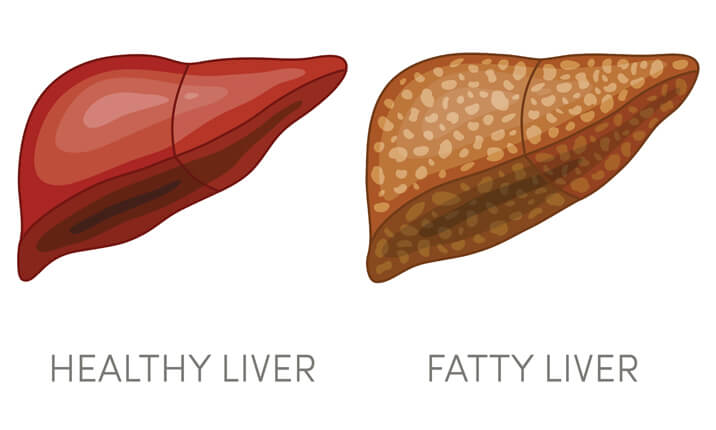

بیماریهای کبد انواع متعددی داشته و هرکدام بهنوعی به این اندام حیاتی آسیب وارد میکنند. کبد چرب یکی از شایعترین بیماری های کبد است که به دلیل تجمع چربی در آن ایجاد میشود. کبد چرب که با نام استئاتوز کبدی نیز شناخته میشود، زمانی اتفاق میفتد که چربی در کبد تجمع پیدا کند.

وجود مقدار کمی چربی در این اندام طبیعی است. اما تجمع بیش از حد آن میتواند به یک مشکل اساسی تبدیل شود. اگر بیش از ۵ تا ۱۰ درصد از وزن کبد شما چربی است احتمالا به این بیماری مبتلا هستید. کبد دومین ارگان بزرگ بدن است. این عضو، به فرآوری مواد غذایی کمک میکند و مواد مضر خون را فیلتر میکند. گاهی این بیماری را بیماری خاموش کبدی مینامند، به این دلیل که میتواند بدون ایجاد علائم رخ دهد.